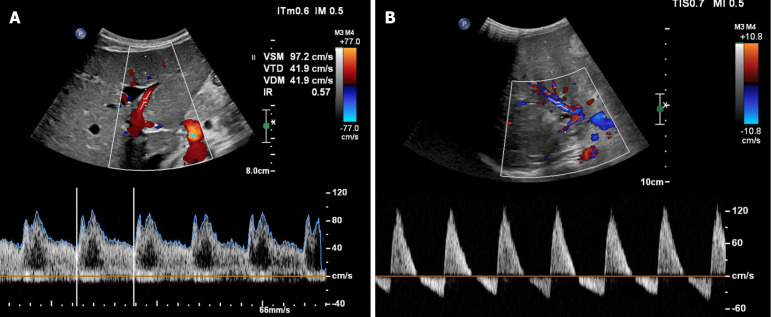

成人门静脉高压和肝硬化与肝脏和体循环严重的血流动力学改变有关。在肝硬化进展过程中,循环变得高动力,导致心脏、肺和肾脏的后果。肝硬化成人也会出现肝硬化心肌病,伴有收缩和舒张功能障碍以及电生理异常。这篇文章提供了正常肝脏血流动力学的最新进展,简要介绍了肝硬化成人的肝脏和全身血流动力学,并描述了肝硬化儿童的肝脏和全身血流动力学。本综述试图阐明肝硬化儿童的肝脏和全身血流动力学是否会像成人一样发生改变。这些血流动力学紊乱的特征有助于更好地理解儿童肝硬化的肝脏和全身生理病理。

Portal hypertension and cirrhosis are associated with severe hemodynamic changes in hepatic and systemic circulation in the adult population. During cirrhosis progression, circulation becomes hyperdynamic, with cardiac, pulmonary and renal consequences. Cirrhotic adults also present with cirrhotic cardiomyopathy, with systolic and diastolic dysfunction and electrophysiological abnormalities. This article provides an update on normal liver hemodynamics, a brief reminder of the liver and systemic hemodynamics in cirrhotic adults, and a description of liver and systemic hemodynamics in cirrhotic children. This review attempts to clarify whether liver and systemic hemodynamics are altered in cirrhotic children like they are in adults. The characterization of these hemodynamic disturbances could contribute to a better understanding of hepatic and systemic physiopathology in pediatric cirrhosis.